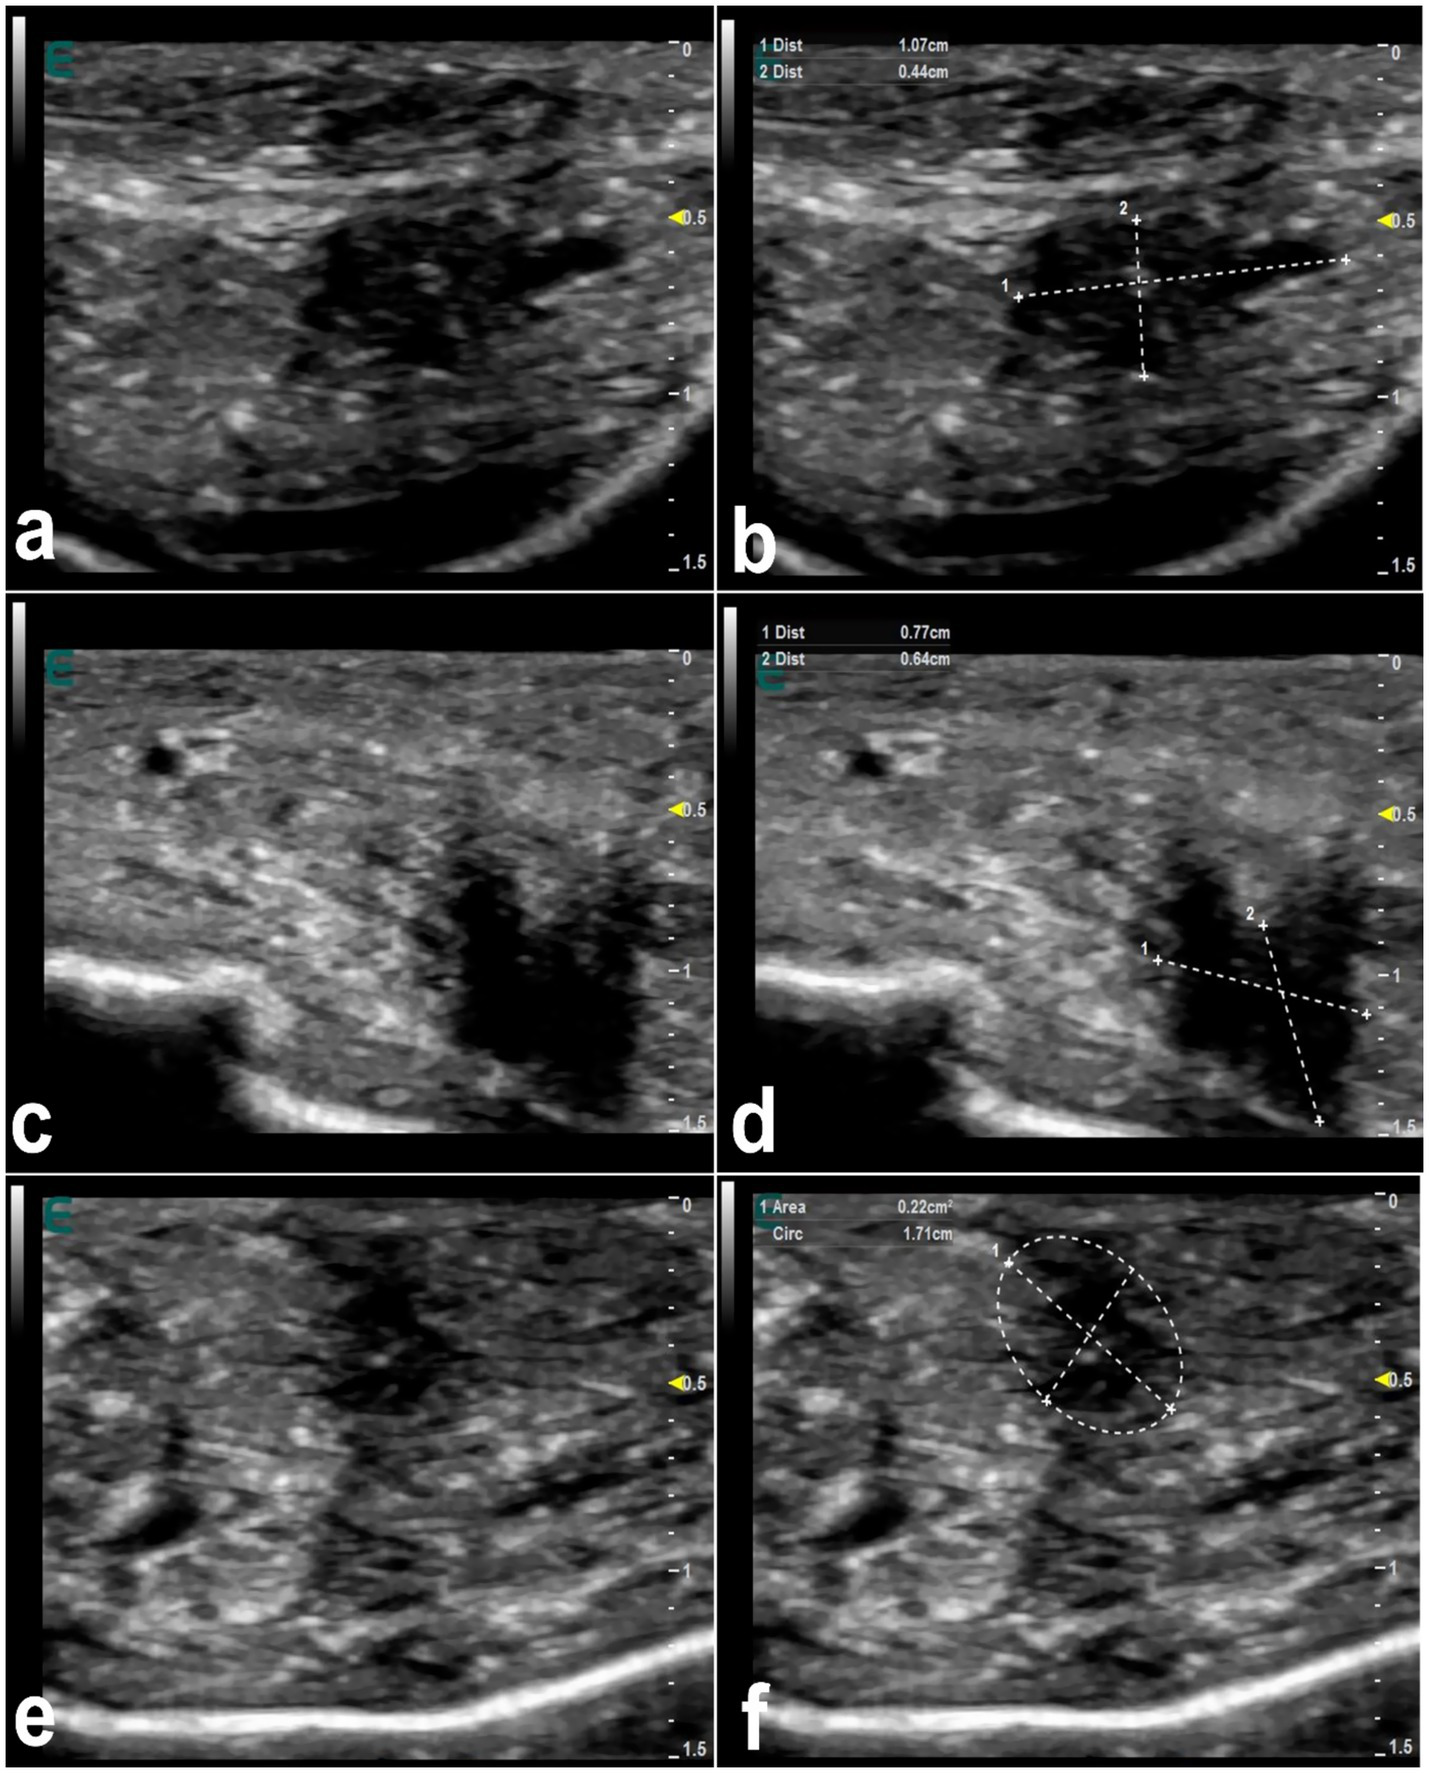

Figure 5 shows mapping of the lips in a healthy camel showing different locations where injected filler materials are commonly injected. In healthy camels, the dermis appears hyperechoic, contrasting with the hypoechoic subcutaneous tissue (16). Filler substances, even those approved by regulatory agencies, can cause in humans detectable changes in tissue structure (63). Injected fillers in dromedary camels typically appear as anechoic or hypoechoic areas on ultrasound, presenting as single or multiple deposits of varying size. In affected camels, the boundary between the dermis and subcutaneous tissue becomes indistinct (Figure 6). Fillers in the firm edges of the lips exhibit hypoechoic signals, with the overall sonographic pattern of injected lips appearing heterogeneous (Figure 7). Lip nodules are visualized as either isoechoic structures with a hypoechoic rim or as hypoechoic lesions with an echogenic center (Figure 8).

Ultrasonographic appearance of injected fillers in the upper lip of 3 female dromedary camels (a,c,e). The injected filler appears anechoic to hypoechoic and was imaged in the form of small or large, single or multiple deposits. It is difficult to distinguish the subcutaneous tissue from the dermis. Images (b,d,f) represent a schematic representation of the images (a,c,e), respectively [Reproduced from (44)].

Figure 7

Ultrasonographic features of hardened tip of the lips in 3 dromedary camels with injected fillers (a,c,e). The injected filler appears hypoechoic and the scanning patterns of the injected lips appear heterogeneous. Images (b,d,f) represent a schematic representation of the images (a,c,e), respectively [Reproduced from (44)].

Figure 8

Ultrasonographic features of lip nodules in 3 camels as a result of filler injections (a,c,e). They appear as either isoechoic with a hypoechoic rim or hypoechoic with an echogenic center. Images (b,d,f) represent a schematic representation of the images (a,c,e), respectively [Reproduced from (44)].